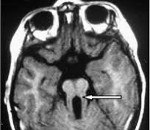

Самым типичным диагностическим признаком синдрома Жубер является наличие так называемого «симптома молярного зуба» - характерные изменения на МРТ головного мозга, внешне похожие на разрез зуба. Это проявление говорит о наличии нарушений формирования стволовых элементов мозга. Также на магнитно-резонансной томографии часто определяется недоразвитие червя мозжечка, гипоплазия мозолистого тела, гидроцефалия, расширение желудочков, энцефалоцеле и другие аномалии развития головного мозга. У взрослых больных синдромом Жубер нередко выявляются признаки поражения внутренних органов - поликистоз почек, фиброз печени, нарушения сердечного ритма. При осмотре у офтальмолога часто обнаруживаются непроизвольные аномальные движения глаз (нистагм), колобома, дистрофия и дегенерация сетчатки.